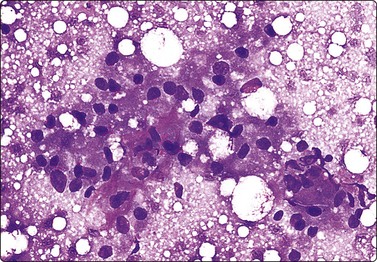

Breast tissue in pregnancy and lactation (Fig. 7.8)

image image image

Fig. 7.8 Lactating breast

Dispersed acinar cells with abundant pale and fragile cytoplasm, rounded nuclei and prominent central nucleoli; background of lipid secretions (A, MGG, HP; B, H & E, HP oil); (C) Corresponding tissue section (H&E, IP).

Criteria for diagnosis

Cellular smears,

Poorly cohesive, mainly dispersed epithelial cells of acinar type,

Cells have abundant fragile cytoplasm with secretory vacuoles and frayed borders,

Rounded vesicular nuclei and central nucleoli,

Dirty background due to lipid secretion and stripped nuclei with prominent nucleoli,

Single bipolar nuclei difficult to find.

FNB is very useful in reducing surgical intervention to a minimum during pregnancy and lactation. The pattern seen in FNB smears of ‘lumps’ in a pregnant or lactating breast can be problematic to inexperienced eyes and cause concern for malignancy.93,94 Smears are usually cellular. The cells are enlarged and arranged in loose groups or singly. The cells have an abundant fragile cytoplasm, vacuolated and finely granular. Nuclei are round, central, larger than the usual ductular cells, and have distinct small nucleoli (Fig. 7.8B). Some epithelial nuclei are stripped of cytoplasm. Single naked bipolar/oval nuclei are difficult to find. The background of abundant milky secretion with numerous lipid droplets seen as vacuoles is characteristic of actively secreting breast tissue and is the main clue to the diagnosis (Fig. 7.8A).